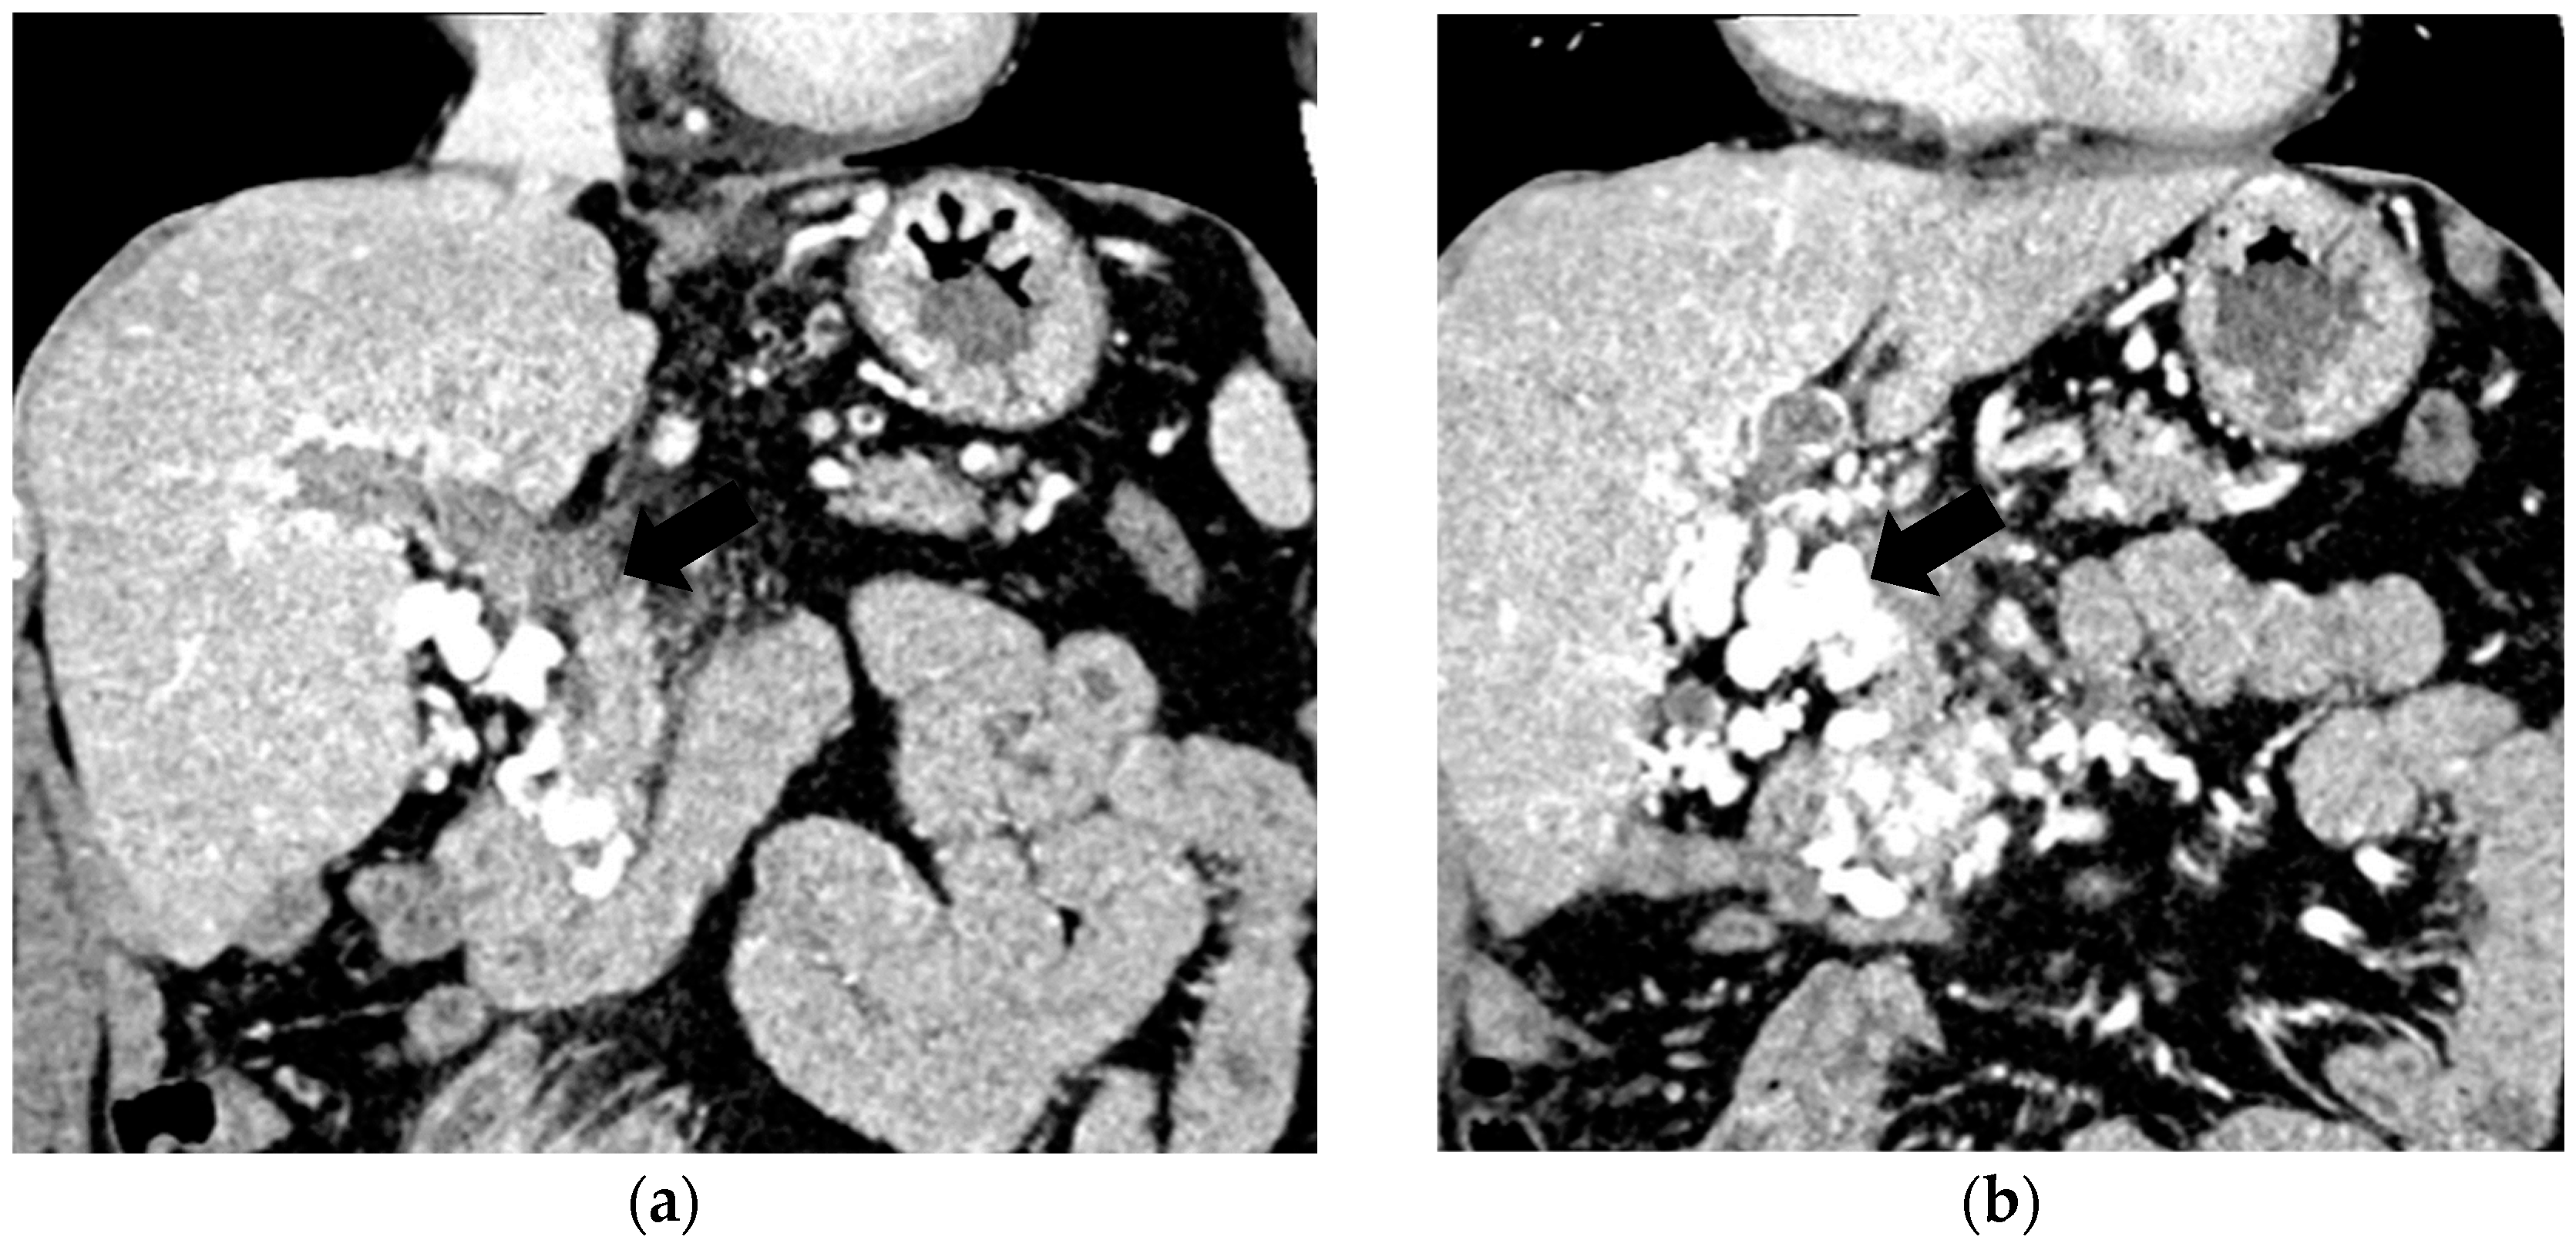

The diagnosis of PVT and PC is made by imaging procedures (transabdominal ultrasound with a Doppler or contrast-enhancing computed tomography scan, magnetic resonance imaging, or angiography in the case of therapeutic intended procedures) [1,3,12,13,14,21,29]. Transabdominal ultrasound is a reliable procedure in 60–100% of cases, with an anechoic aspect in recent cases (requiring Doppler examination or CEUS) and a hypoechoic or hyperechoic aspect in chronic cases [22,29]. Doppler examination may show an anechoic or hypoechoic thrombus and a slower (<15 cm/sec) or absent portal blood flow, and is considered the gold standard (color Doppler) for the diagnosis of PC [1], with a sensitivity and specificity of 95% (Figure 1 and Figure 2) [22]. CEUS can help the diagnosis of benign or malignant PVT, can characterize associated focal liver lesions [30], allows a better characterization of PVT [31], and also permits better detection of PC—Figure 3 and Figure 4 [32]. CT scan and MRI (Figure 5 and Figure 6) are more accurate for the evaluation of liver causes (HCC, abscesses, and other tumors) or other local causes (pancreatitis, diverticulitis, and appendicitis), and for complications (bowel infarction or perforation), and may show permeability of the portal venous system and the flow direction [1,22]. Malignant PVT has intra-thrombus arterial signals on CT, MRI, and/or CEUS, with portal vein diameter frequently 23 mm or above, and with the presence of the tumor at imaging examination (Figure 4 and Figure 6) [21].

Figure 3.

CT scan in a patient with recent surgery for transverse colon adenocarcinoma. (a) The enlarged portal vein, with intraluminal thrombus and peri-gastric collateral circulation, indicated by black arrow. (b) A 59/34 mm portal cavernoma, indicated by black arrow.

Transabdominal ultrasound with Doppler protocol (Figure 1a,b and Figure 2a,b), CT scan (Figure 3a,b), and MRI (Figure 4a,b) were used for the diagnosis in 88.9, 75.1, and 15% of cases, respectively. CEUS was used for the diagnosis in 49 cases (25.9%) but in only 29 cases was it used for the evaluation of the thrombus, and in two cases for cavernoma diagnosis (Figure 5a,b and Figure 6a,b).